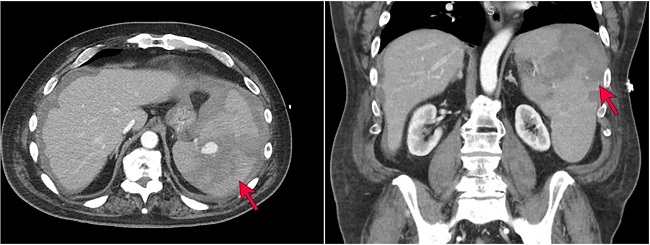

The patient is a 70-year-old man with a past medical history of hypertension, insulin-dependent diabetes mellitus, meningioma status post resection, and colon cancer status post resection who presented to an outside hospital with acute onset abdominal pain and was found to have a 10 cm spontaneous grade IV splenic laceration with active extravasation (Figure 1) splenomegaly, and external iliac lymphadenopathy (4.1cm in greatest dimension)..